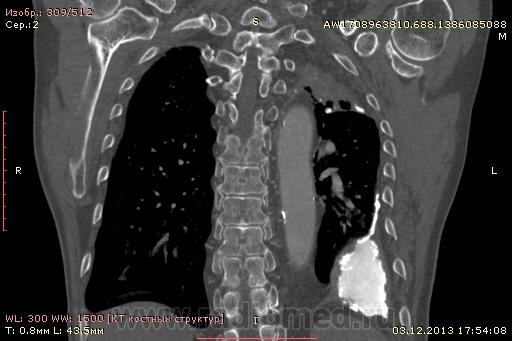

Доброго времени суток уважаемые форумчани! :)Провели исследование КТ грудной клетки с контрастированием, для выявления аневризмы грудного отдела аорты. В результате увидели это:

??? Аневризму честно не вижу (мало опыта в определении аневризм). Тромбоз в бассейне верхней полой вены. В левом легком обызвествленные плевральные шварты? как исход осумкованного плеврита неизвестной давности?

на VRT-реконструкции. плотность до + 1000 HU. видел такое как посттуберкулезные обызвествления плевры, надо завтра ещё раз поговорить с лечащим врачом, может ошиблись

Ребята, вы что, какая жидкость? Чистая известь, посмотрите в костном окне. Отставить натив (в данном случае, хотя для аневризм он обычно нужен). Отставить тромбоз верхней полой вены (потоковые артефакты, не дело вены в артериальную фазу оценивать). Отставить аневризму  аорты, поперчник восходящего отдела на уровне легочного ствола 42мм. А вот легочная гипертензия, здравствуй: поперечник легочного ствола - 37мм, ПЛА - 25мм, ЛЛА - 25мм, НАо - 25-34мм.

Для справки: холестериновые камни имеют плотность менее 100 ед.Н. Имеющаяся хренотень в левом гемитораксе имеет плотность больше костной, до 1500 ед.Н. Вопрос: какая химико-физико-биологическая реакция может способствовать превращению мягинькаво холестерина в термоядерную плевральную лепёшку?)

В анамнезе перенёс туберкулёз неизвестной давности.